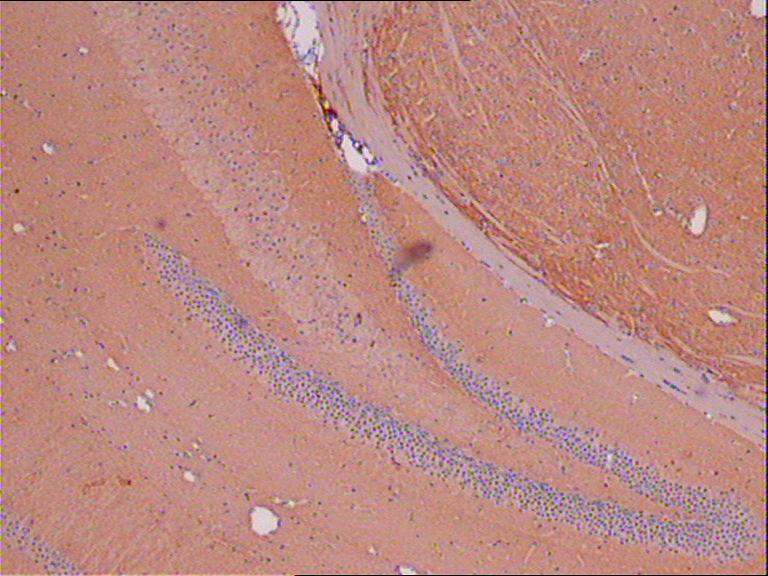

ÇóÖú ÃâÒß×éÖ¯»¯Ñ§È¾É«ÖгöÏÖ°×É«£¬ÎÞÑôÐÔ½á¹û